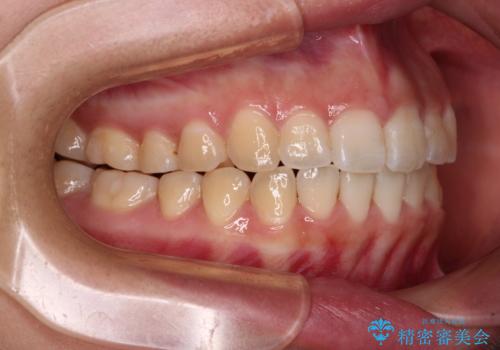

- 上下の前歯が非接触であることと、それに伴う口元の閉じにくさを気にして来院された患者様です。

奥歯の咬み合わせを見ると、上顎が下顎に対して相対的に前方にありました。

口元の閉じにくさを改善するためには、上顎臼歯を後方に移動させた咬み合わせにする必要があります。

インビザライン単体で改善することも可能ですが、達成する可能性が高くないため、カリエールディスタライザーという補助装置を併用して、より確実性を上げることとしました。

奥歯の咬み合わせを改善しながら、並行してインビザラインで歯列を整えることとしました。

カリエールディスタライザーを併用したことで、確実かつ短期間で治療を終えることができました。